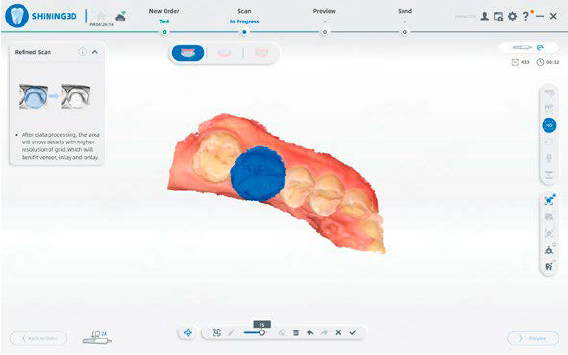

INTERFACCIA INTUITIVA

Un design pulito e lineare per un processo di scansione più efficiente e senza interruzioni.

SCANSIONE INTELLIGENTE

Un design pulito e lineare per un processo di scansione più efficiente e senza interruzioni.

INDICATORE DI QUALITÀ

Le aree incomplete vengono evidenziate in grigio, facilitando l’individuazione delle zone da ripassare per una qualità ottimale.

DETTAGLI RAFFINATI

Riproduzione accurata della morfologia e delle preparazioni con fedeltà eccezionale.